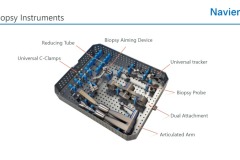

Cranial, Biopsy, Spine, ENT

5.JARUM BIOPSY TIDAK TERGANTUNG PADA SATU MEREK. Hemat biaya

Tracking system

• Infrared optical tracking system

• Live video stream

• 0.2mm calibration accuracy

• Permanent markers

• Reusable and sterilizable instruments

• Biopsy trajectory planning and navigation